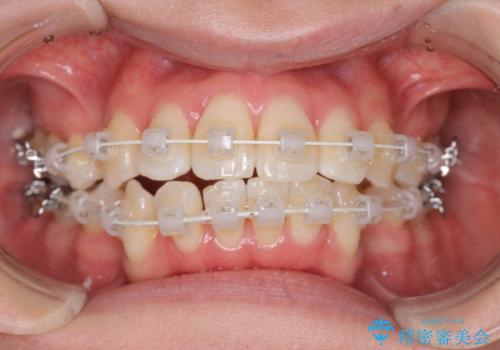

- 審美装置

上顎にはMI(マイクロインプラント)を埋入して固定源とすることで出っ歯の改善を図りました。

少しスペースクローズに時間がかかりましたが、MIを用いたワイヤー矯正で